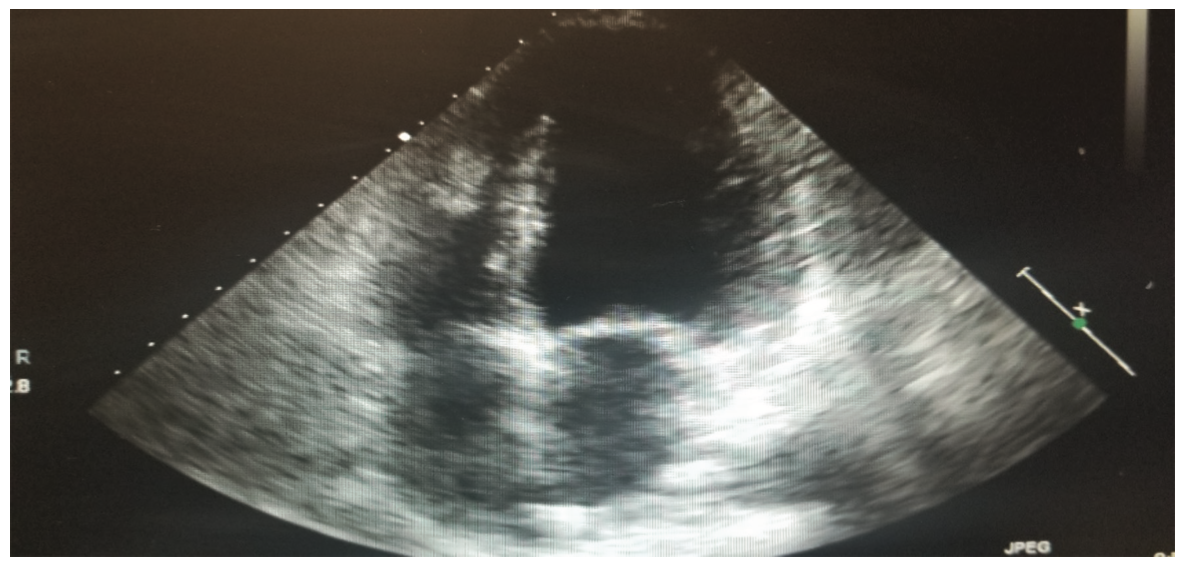

This is a 58-year-old female with a history of tuberous sclerosis. Transthoracic echocardiogram images demonstrated a heterogeneous mass in the mid right ventricle attached to the septum and the moderator band (Figures 1-6). The mass looked similar to what was seen on a transthoracic echocardiogram from a year prior.

One of the major differentials for this mass was thought to be cardiac rhabdomyoma, given the patient’s history of tuberous sclerosis with known renal angiomyolipomas. Cardiac rhabdomyomas are usually associated with tuberous sclerosis complex, which is a genetic disorder characterized by hamartomas in multiple organs. Rhabdomyomas may develop at any location in the heart, but the most common locations are ventricular and septal walls.